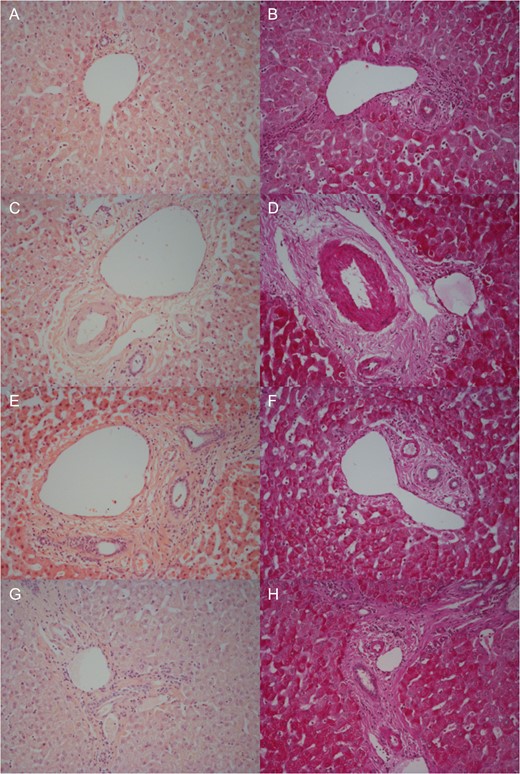

Specimens taken 3 hourly and on completion of NMP-L from each lobe were examined by H&E and PAS staining. Blinded assessment was performed by a pathologist.

Moderate sinusoidal vasodilatation was noted throughout although milder post-splitting (Fig. 4A, C, E and G). There were no necrotic hepatocytes post-splitting (Fig. 4G). Macrovesicular steatosis was low (< 10%) pre-NMP-L (Fig. 4A) and remained unchanged (Fig. 4G). There was no intrahepatic bile duct injury. The trend was for increasing PAS staining over time (Fig. 4B, D, F and H).

Representative histological samples to assess architectural integrity and necrosis by H&E staining (A, C, E, G) as well as glycogen content using Periodic acid-Schiff staining (B, D, F, H). Samples taken prior to commencement of NMP-L (A, B), after 3 h of NMP-L (C, D), after 6 h of NMP-L (E, F) and after parenchymal splitting with concurrent NMP-L (G, H).